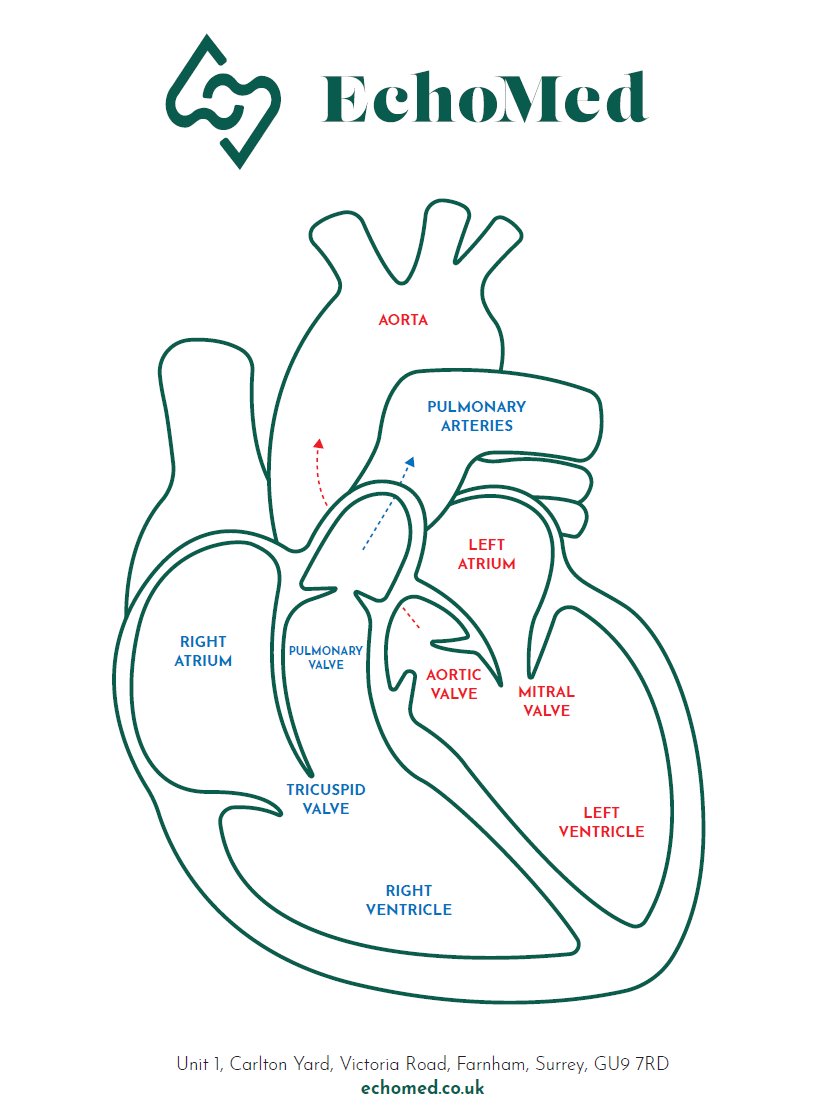

We use this annotated diagram of the heart to explain scan results to our patients. #echofirst EchoTalk Echocardiography Echocardiography British Heart Foundation BSEcho